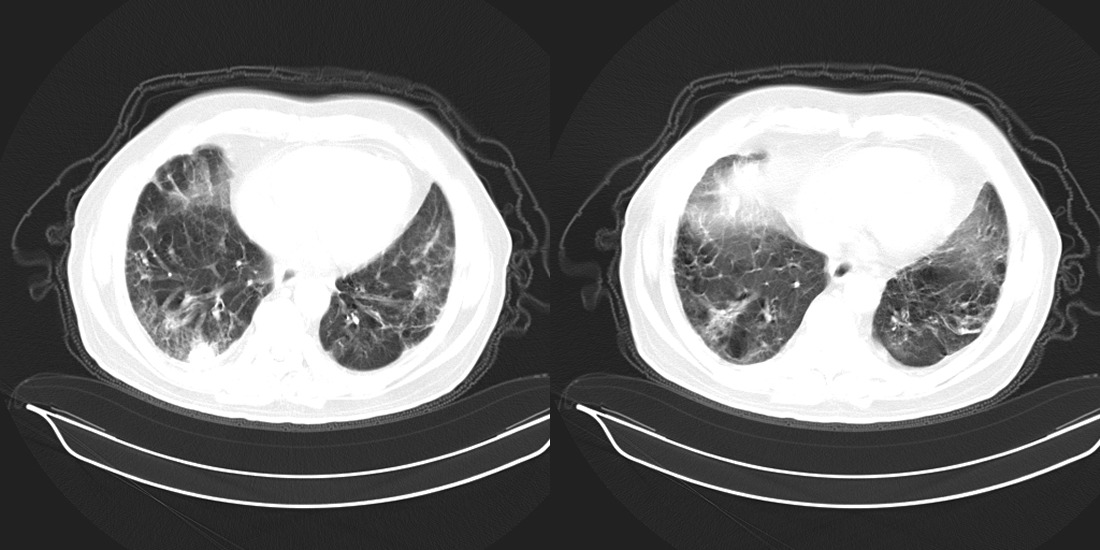

以下是引用zsl6918在2008-2-14 12:15:00的发言:[br]慢支并感染,肺气肿,肺间质纤维化,肺动脉高压。

以下是引用liuyue在2008-2-14 17:25:00的发言:[br]慢支并感染,肺气肿,肺间质纤维化,肺动脉高压 .肺大泡.[br]

以下是引用随光逐影在2008-2-15 11:10:00的发言:[br]1)慢性支气管炎并肺部感染。2)肺间质纤维化。3)肺气肿(多发性肺大泡形成)。4)肺动脉高压。